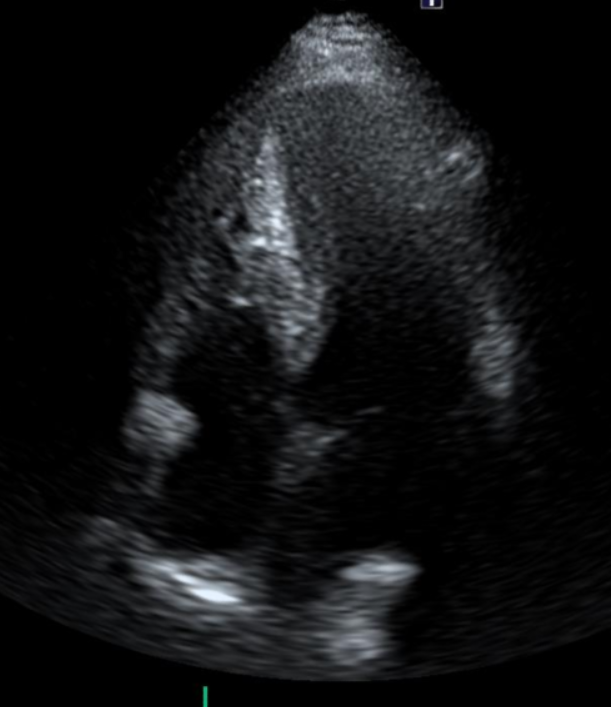

2. 심장초음파

심장초음파에서 좌심실 중격/벽의 현저한 비후와 유출로 협착 의심. 비후성 심근증 가능성이 높아 추가 정밀 검사 및 치료 계획 수립을 위해 상급병원 연계.

• 심장초음파: 좌심실 비후 심장초음파: 좌심실 비후

• 심장초음파: 좌심실 유출로 협착 의심 심장초음파: 좌심실 유출로 협착 의심